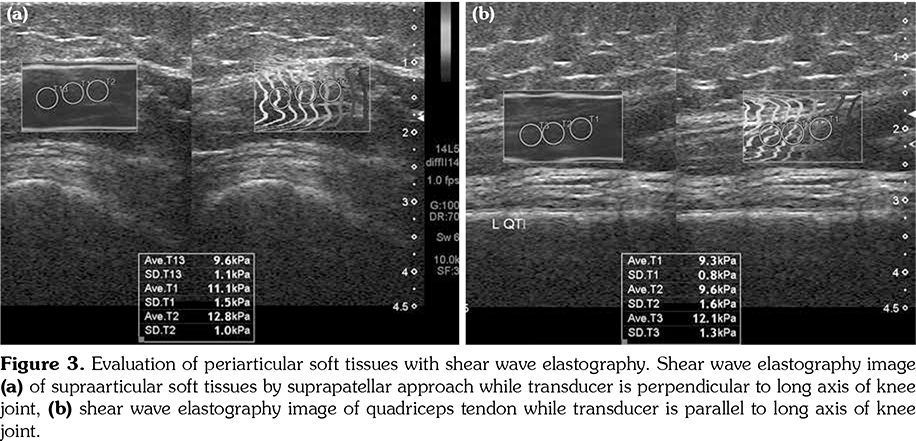

All patients and healthy volunteers were screened with Canon Aplio 500 Platinum US device (Canon Medical Systems, Tokyo, Japan) equipped with SMI, PD and SWE functions. All participants were examined in supine position and their knees were in extension (Figures 1, 2). Once the gray scale US examination confirmed the arthritis based on synovial thickening, joint effusion and periarticular echogenicity, then SMI and SWE were performed to the supraarticular and infraarticular soft tissues concerning the synovium and periarticular soft tissues. VI is a novel parameter determined for SMI and PD corresponding the ratio of colored pixels to the total pixels within the selected region of interest (ROI). VI was calculated automatically on colored SMI and PD images over the selected rectangular shaped ROI with edges measured 5x15 mm (Figure 3). Mean VI values were calculated by averaging results of three different acquisitions of PD and SMI. The ROI was placed perpendicular to the long axis of the knee joint at the supraarticular and infraarticular locations including the synovium and periarticular soft tissues. On SWE evaluation, the QT and PT were demonstrated along with their long axis. Three different ROIs for SWE were performed from the tendon halves closer to the knee joints. Each ROI was in circle shape and 3 mm in diameter. We depicted mean elasticity for PT, QT, supraarticular soft tissues (SAST) and infraarticular soft tissues (IAST) (Figures 4, 5).

The mean SWE values obtained from SAST including synovium and suprapatellar fat pad was 10.7±2.5 kPa in study group and 9.9±2.3 kPa in the control group (p>0.05). The mean SWE values obtained from IAST including synovium and infraarticular fat pad was 9.8±2.4 kPa in study group and 9.4±2.3 kPa in the control group (p>0.05). No significant difference was found among SWE values of periarticular soft tissues among study and control subjects. The mean SWE of PT was 19.7±6.9 kPa in the study group and 16.5±4.8 kPa in the control group. Although the mean QT SWE (19±6.1 kPa) was higher in the study group than the control group (15.7±4.8 kPa), the differences among the mean SWE values of QT and PT failed to reach statistically significant levels (p>0.05) (Table 1).